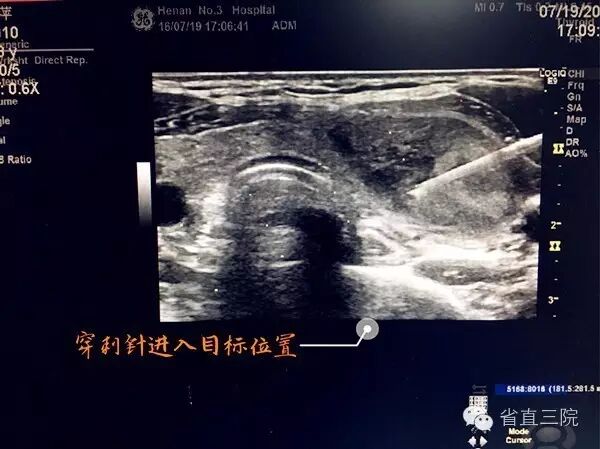

7月20日下午,我院西区超声科在张永祥老师的带领下又成功的进行了两台超声引导下穿刺术:超声引导下颈部肿物穿刺、超声引导下甲状腺穿刺。目前,我院超声引导下定位穿刺术已有了我们自己的方式和模式,成为相当成熟、完善的诊断技术,也成为我院超声科科室特色。

我院西区超声科在王春荣主任和张永祥老师的带领和指导下已成功开展了超声引导下经皮胆囊穿刺引流术、肝癌射频消融术、小肝癌无水酒精灭活术、肝囊肿及肝脓肿穿刺、肾活检穿刺术、甲状腺、乳腺及淋巴结活检穿刺术等300多例,最大程度上提高了病变组织的阳性检出率,增加了诊断的准确性,为临床手术提供了可靠的依据,获得了临床大夫的一致好评。

超声波的指向性能够对病变进行相当准确的定位,而且能实时观察组织解剖结构的动态变化,其准确性和安全性是其他影像手段不可比拟的,超声引导下穿刺技术就是在实时超声影像的监视和引导下,针对体内病变或目标进行穿刺的临床技术,超声的引导在最大程度上避免了对目标周围组织的损伤,穿刺后还能立即对穿刺部位及穿刺路径进行观察,及时发现、处理可能出现的并发症。